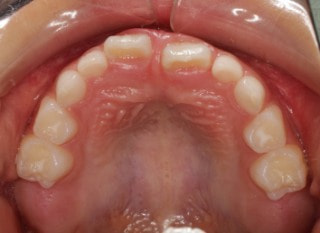

小児期の第二段階

終了時